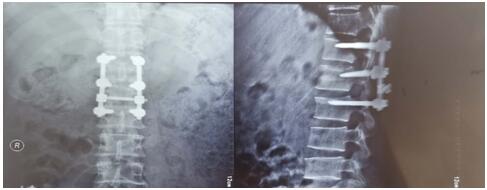

術(shù)后影像學(xué)資料如下:

骨盆骨折多由高能量損傷所致,多伴有合并癥或多發(fā)傷,處理棘手,致殘率高達50%~60%。經(jīng)過孟澤祖主治醫(yī)師、李鵬鵬住院醫(yī)師的精心管理與辛勤付出,患者曹某腰椎骨折術(shù)后病情恢復(fù)良好。于2020年4月1日在全麻下行骨盆粉碎性骨折切開復(fù)位內(nèi)固定術(shù),患者多處骨盆粉碎性骨折,病情復(fù)雜,手術(shù)時間長,術(shù)中出血多。首次采用改良stoppa+右髂后上棘聯(lián)合入路,手術(shù)順利,術(shù)后病情不穩(wěn)定,經(jīng)過主管醫(yī)師孟澤祖與全科骨干醫(yī)師、護士的通力合作與堅守,術(shù)后病情日趨穩(wěn)定。復(fù)查下肢血管超聲提示:未見明顯血栓。患者曹某在我院經(jīng)過標(biāo)準(zhǔn)化、專業(yè)化的綜合治療后,患者病情恢復(fù)良好,神經(jīng)損傷癥狀已基本恢復(fù),傷口I級愈合,患者帶著滿意的笑容康復(fù)出院了。